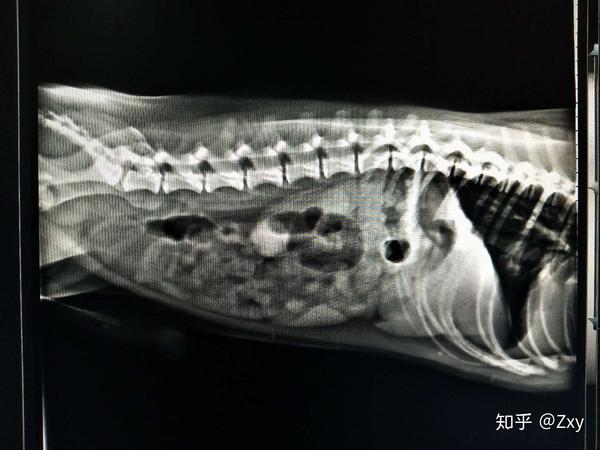

正常犬x光示意图

正常犬x光示意图,正常猫爪x光图片

第一家医院拍的x光

求专业的帮我看看x光片,狗狗喉咙怎么了?在线等!急!